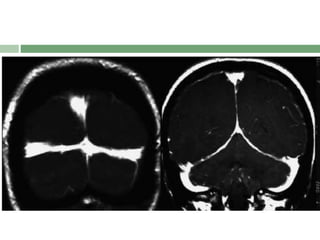

 S- Subdural fluid collections

Acronym : SEEPSfor MRI Features  SEEPS  S- Subdural fluid collections  E- Enhancement of the pachymeninges  E- Engorgement of the venous structures  P- Pituitary enlargement  S- Sagging of the posterior structures